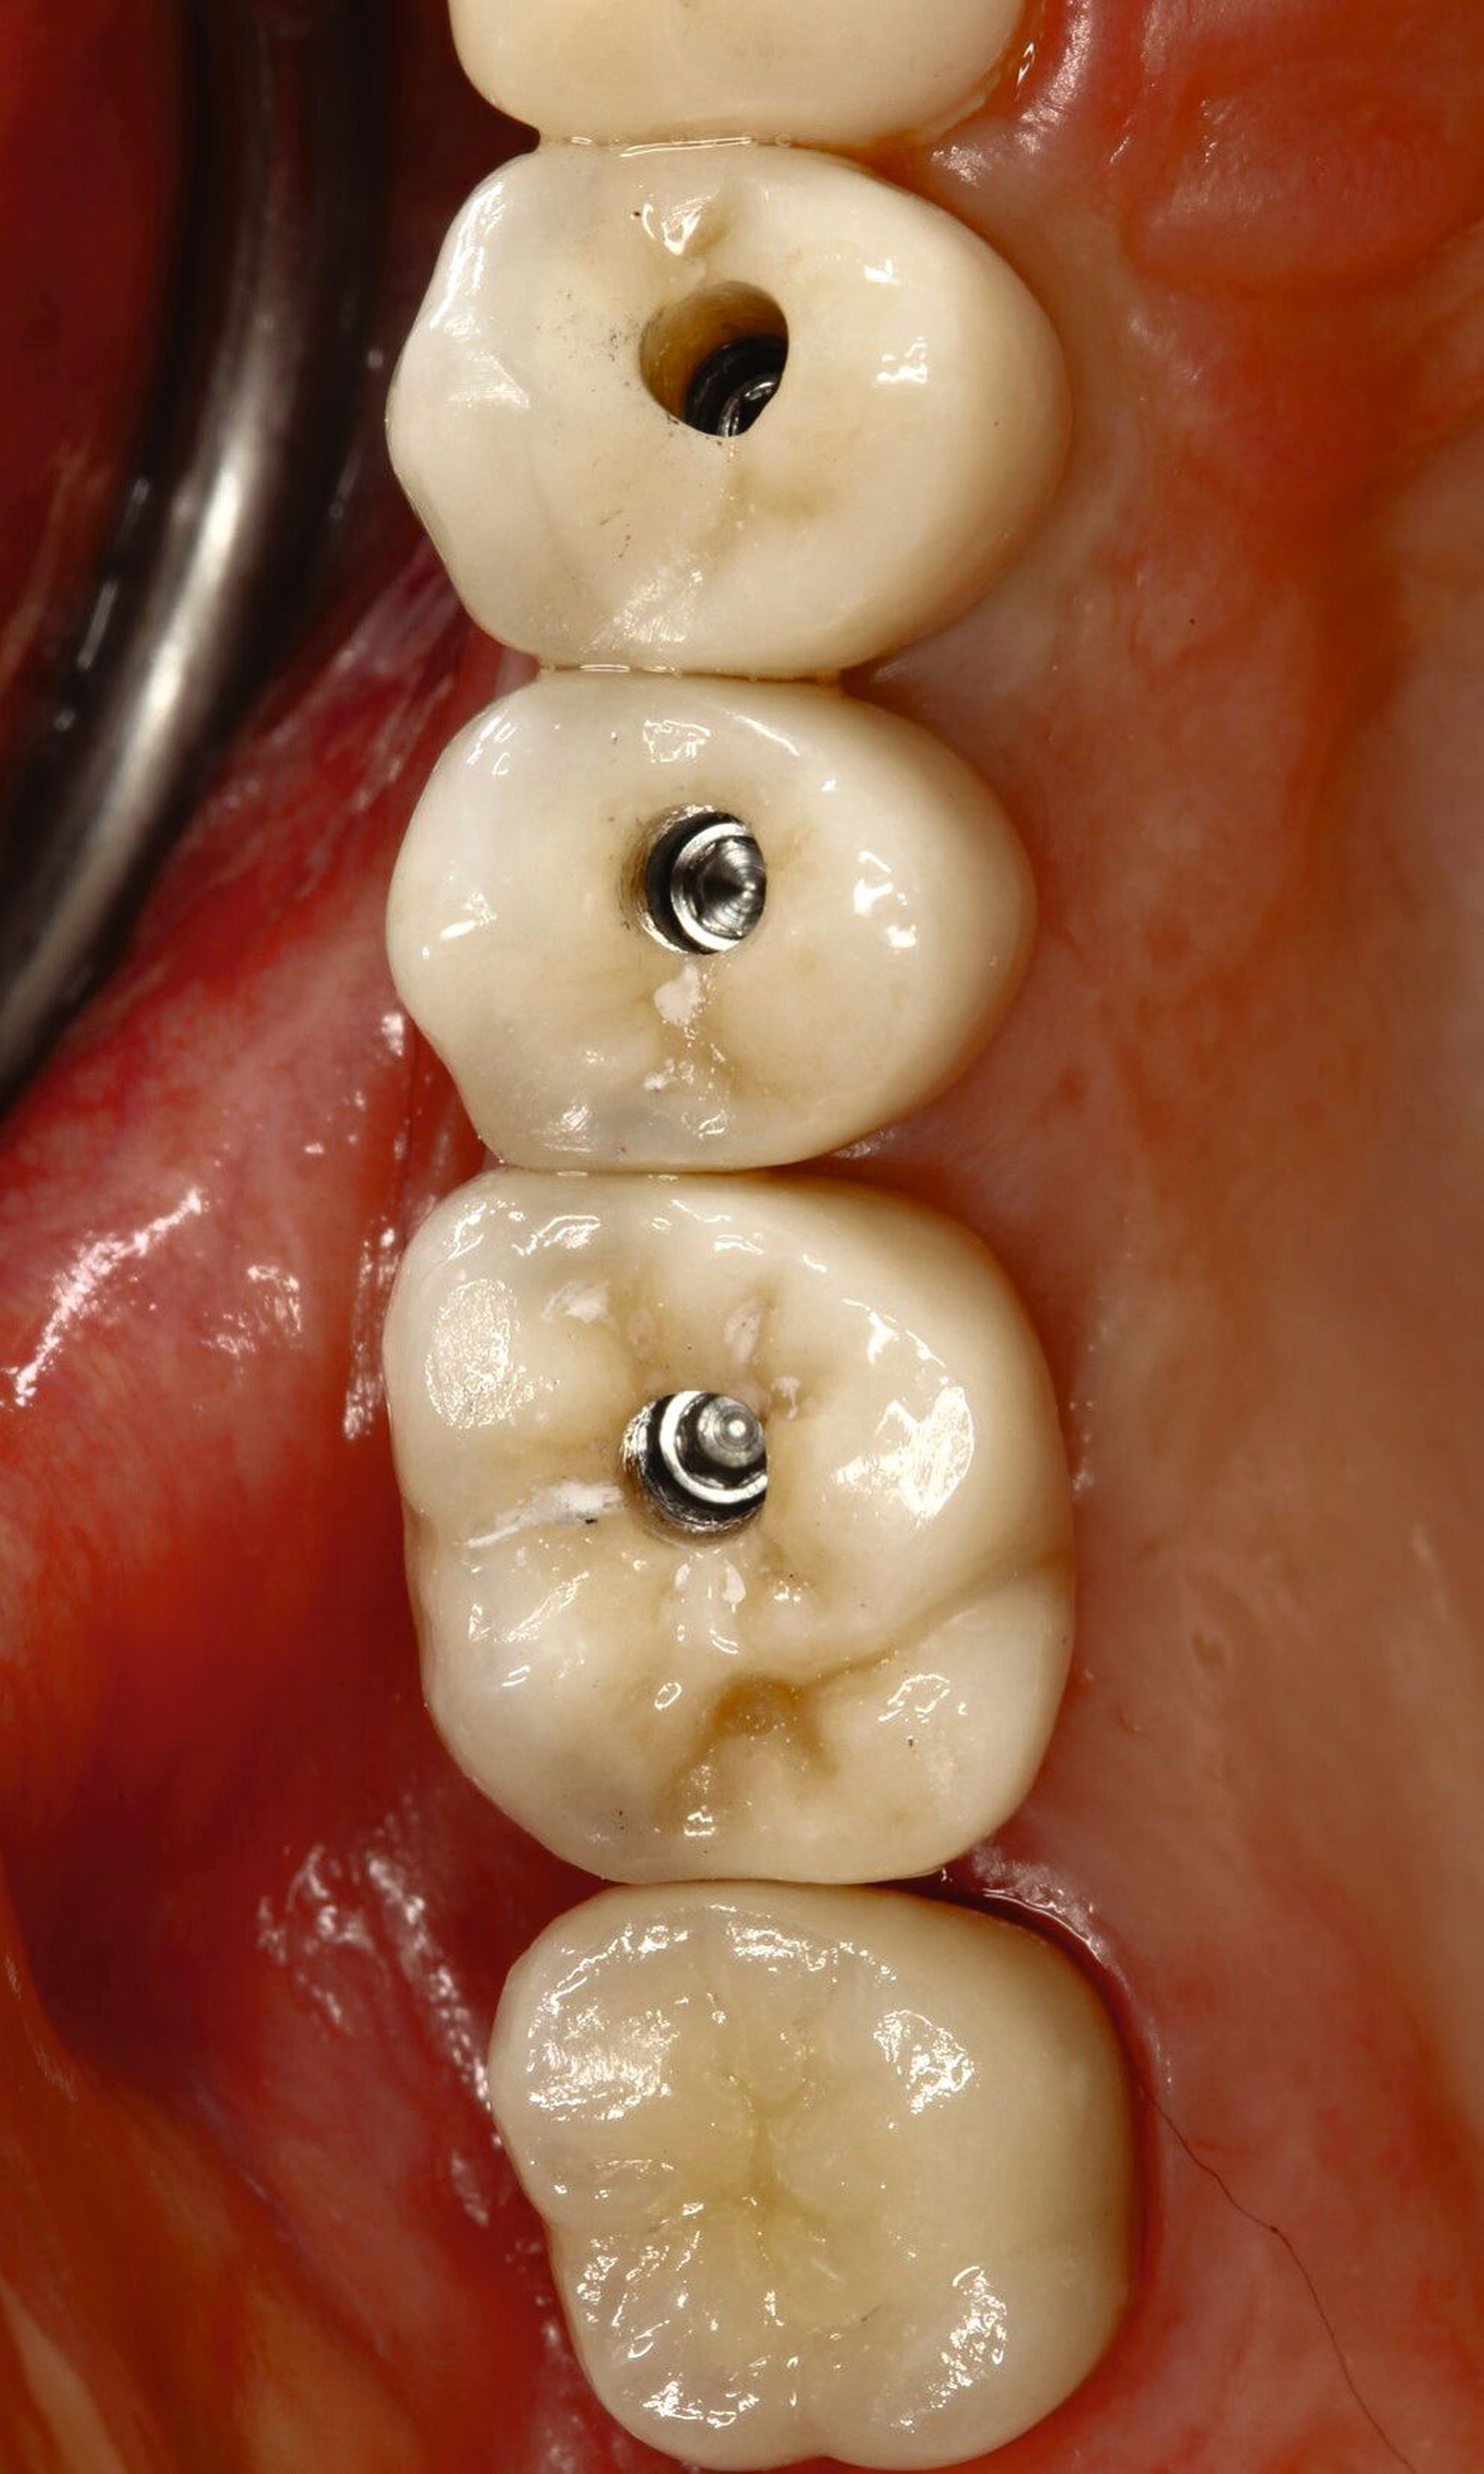

Eine zusätzliche Maßnahme, um das Weichgewebe zu optimieren, ist nicht notwendig und das angestrebte Okklusionskonzept kann umgesetzt werden, wobei die implantatprothetische Restauration nur minimal im Kontakt steht. Dies ist in vielen Fällen nur schwer umzusetzen. Wird die Restauration voll in statischer Okklusion belastet, bekommt die Restauration das Label A. Im vorliegenden Fall wird die Implantatkrone in gewisser Weise von den Nachbarzähnen geschützt, befindet sich aber dennoch in Okklusion (Abbildung 5). Für Implantatkronen, wie in diesem Fall, wird das Okklusionsschema so angepasst, dass die Shimstock-Folie im Schleifkontakt durchgehen kann. Situationen ohne okklusale Parafunktionen stellen ein geringes Risiko dar. Dann entscheidet der Zeitpunkt der Belastung über das Risiko, wobei spät und früh belastete Implantate dasselbe geringe Risiko haben. In unserem Fall zeigt der Patient Anzeichen einer Parafunktion, sodass den Unterkieferbewegungen und der okklusalen Morphologie der Restauration besondere Aufmerksamkeit gewidmet werden muss.

In der vorgestellten Situation wird kein therapeutischer Zahnersatz (Langzeitprovisorium) benötigt, daher bekommt unser Fall das Label S. Kann eine verschraubbare Krone verwendet werden, erhält diese ebenfalls das Prädikat S, die zementierte Restauration wird mit einem höheren Risiko bewertet.

Fall 2 – complex (chirurgisch/prothetisch)

Der zweite Fall zeigt, dass nicht alle implantologischen Behandlungen chirurgisch als straightforward (S) eingestuft werden können. Während im Straightforward-Fall ein Behandler ausreichte, war im komplexen Fall die Expertise von zwei spezialisierten Kollegen nötig. Dies verdeutlicht, dass die Einschätzung der Komplexität vor Behandlungsbeginn entscheidend ist, um den optimalen Behandlungsweg zu wählen und das bestmögliche Ergebnis zu erzielen.